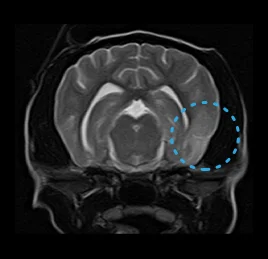

• 수막뇌염

• 허혈성 소뇌경색

• 뇌수두증

• 후두골 이형성 증후군